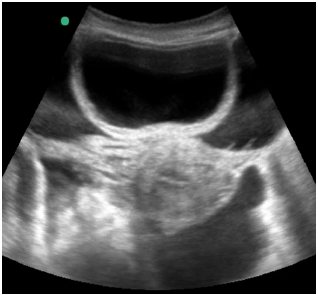

Uma paciente de 55 anos de idade, internada na UTI em razão de quadro de cirrose alcoólica com hemorragia digestiva alta por varizes esofágicas.

Diante do achado evidenciado na ultrassonografia abdominal, o plantonista procedeu à paracentese guiada por ultrassonografia para diagnóstico diferencial, com a qual pretendia diagnosticar